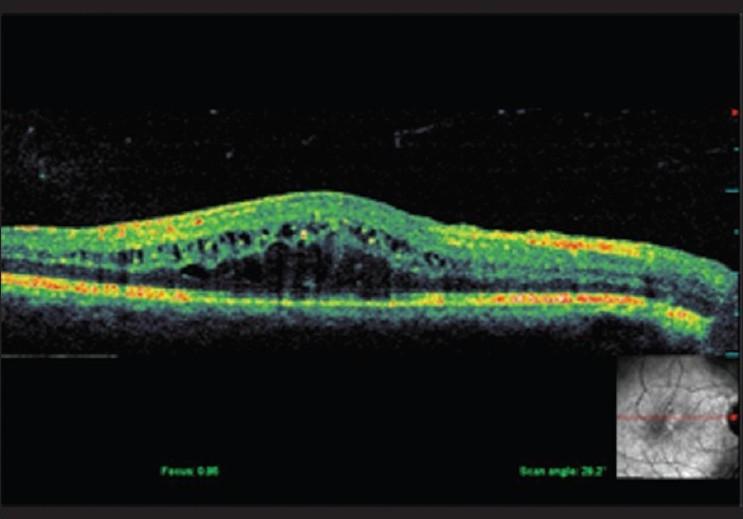

与未经治疗的脉络膜黑色素瘤相关的视网膜下脂质渗出。

Subretinal lipid exudation associated with untreated choroidal melanoma.

Subretinal lipid exudation in an untreated choroidal melanoma is very rare. It is seen following plaque radiotherapy in choroidal melanoma. There is only one case report of untreated choroidal melanoma with massive lipid exudation in a patient with metastatic hypernephroma. We report here a rare case of untreated choroidal melanoma with lipid exudation. Subretinal exudation that is rarely seen following plaque brachytherapy was noted at the borders of this untreated tumor. Lipid exudation partially resolved following brachytherapy.

摘要

未经治疗的脉络膜黑色素瘤很少出现视网膜下脂质渗出。这种情况见于脉络膜黑色素瘤的放射性敷贴治疗后。仅有一例转移性肾细胞瘤患者的未经治疗的脉络膜黑色素瘤伴大量脂质渗出的病例报告。我们在此报告一例罕见的未经治疗的脉络膜黑色素瘤伴脂质渗出的病例。在该未经治疗的肿瘤边缘观察到放射性敷贴治疗后罕见的视网膜下渗出。脂质渗出在放射性敷贴治疗后部分缓解。